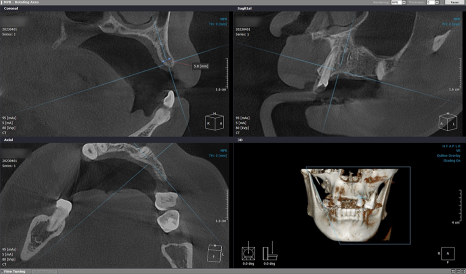

본격적인 치료 전,

픽스처를 심기 위한

치조골 위치를 정확히 파악하기 위해

3D-CT 촬영을 했으며

음식을 씹는 데 불편함이 없으시도록

좌측부터 인공치를 만들기로 했습니다.

환자분 뼈 상태의 해부학적 구조를

면밀하게 파악한 다음

잇몸뼈 높이와 폭, 각도 등을 고려해서

좌측부터 인공 치근을 심었습니다.